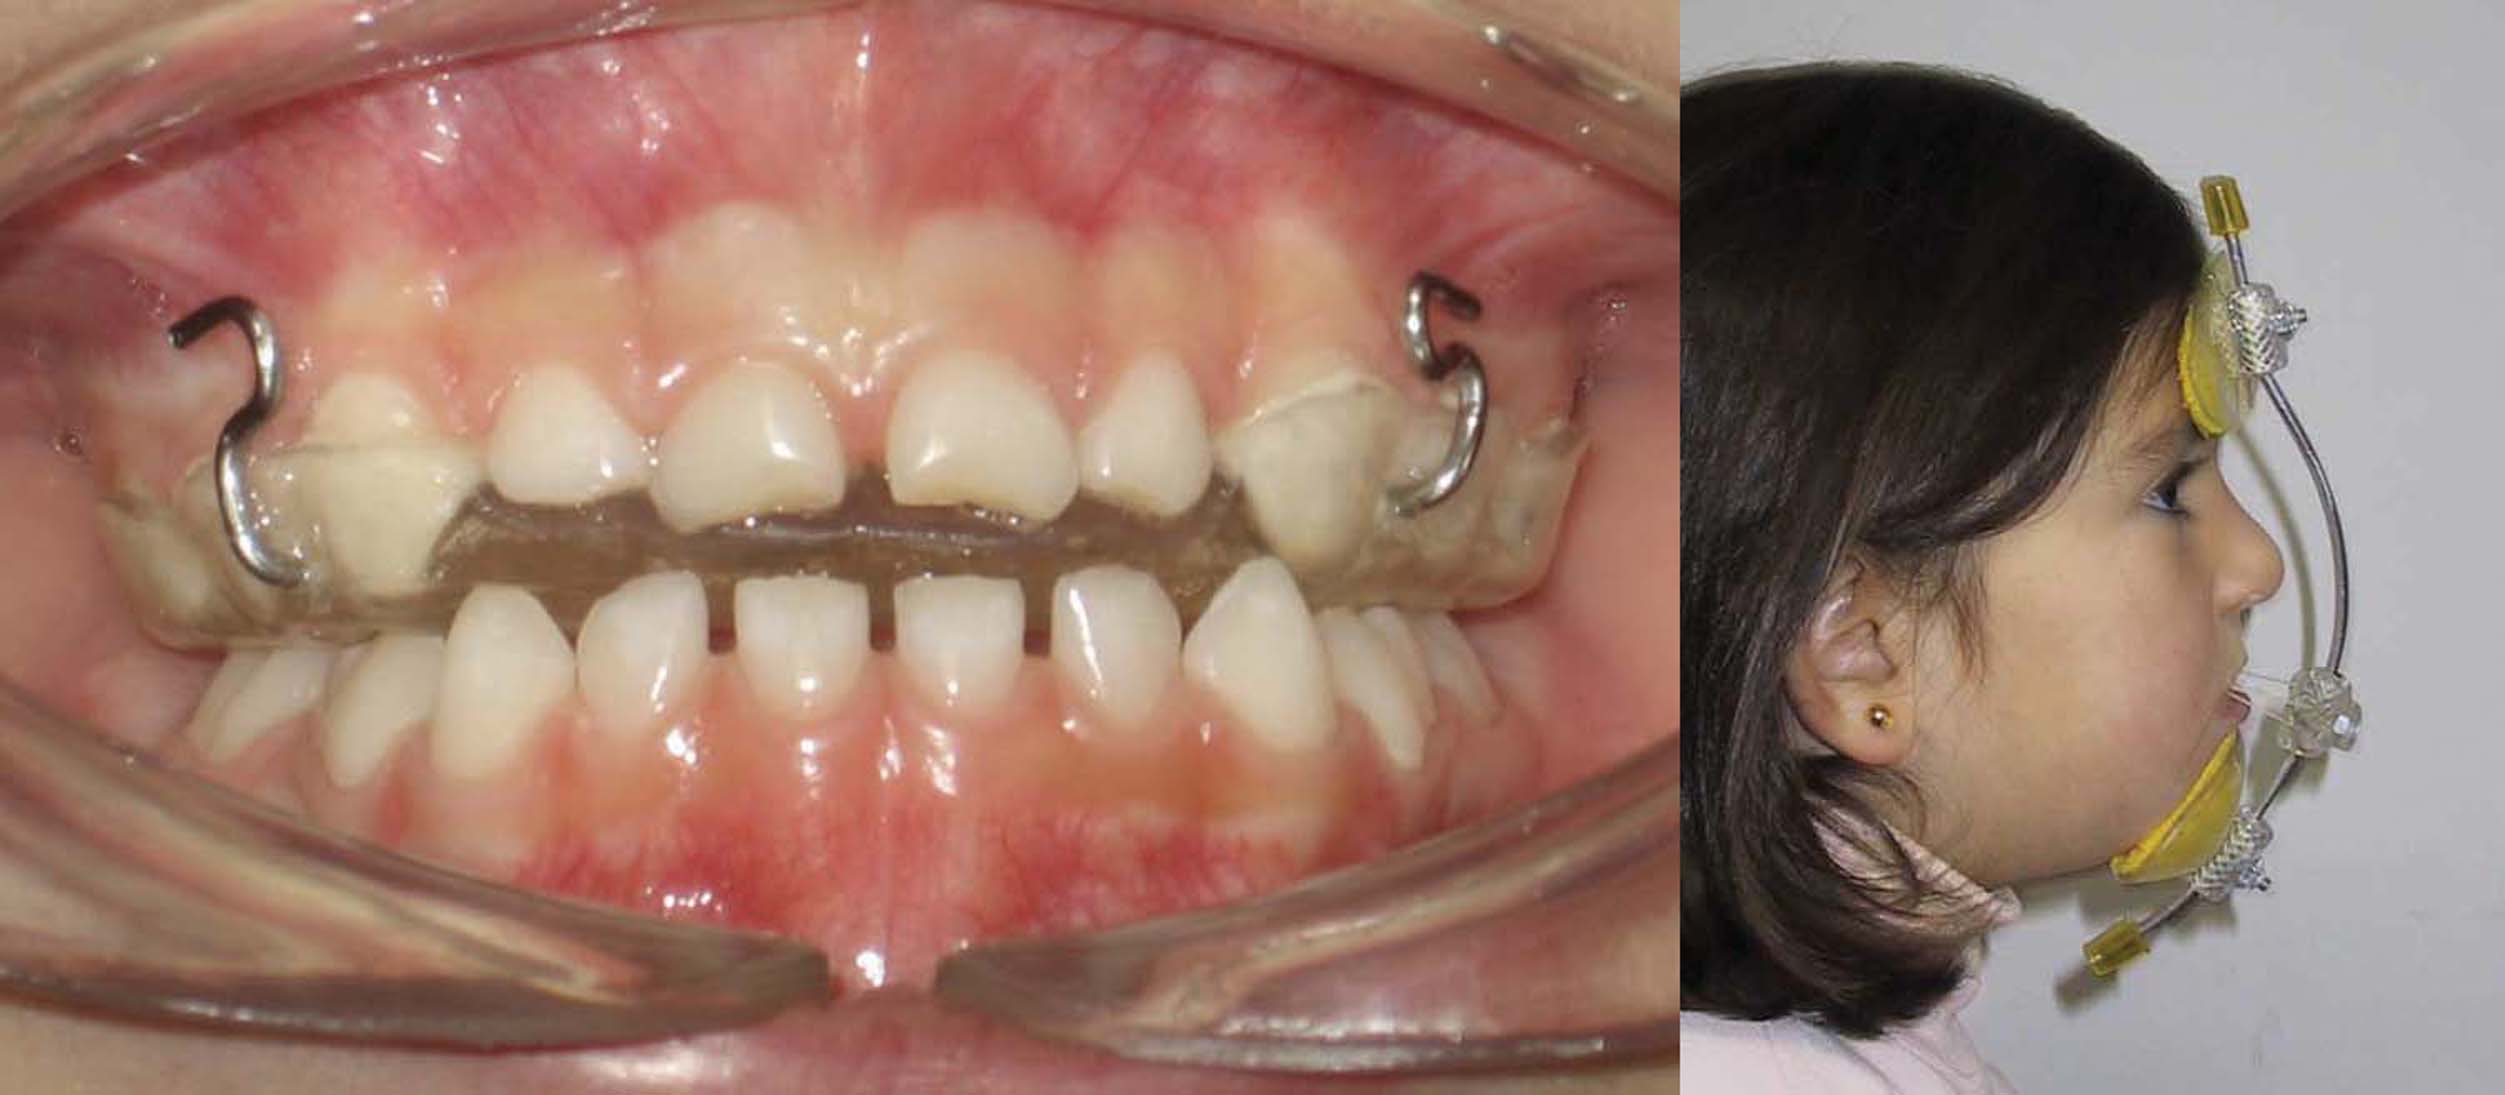

El propósito es presentar una propuesta clínica de intervención en niños basado en la experiencia de ocho años de aplicación piloto de terapias ortodóncicas tempranas en la Universidad de la Frontera en los pacientes de los alumnos de cuarto y quinto año de la Carrera de Odontología, así en consultorios de la región del sur de Chile. Se describen las bases para un adecuado diagnóstico y posterior tratamiento de anomalías frecuentes en niños, así como el desarrollo de la aparatología utilizada. En primer lugar el manejo de malos hábitos en pacientes clase II, luego la tracción frontal en pacientes clase III y finalmente el manejo del recambio en pacientes clase I. Aquellos pacientes que utilizan de buena manera sus aparatos obtienen resultados espectaculares. Por lo que la relación con los padres y la motivación a los niños son elementos fundamentales a la hora de decidir tratar a un niño con entrenadores, máscara de tracción o mantenedores de espacio dinámicos. A pesar de que no evita en todos los pacientes los tratamientos de ortodoncia correctiva, se mejoran las condiciones de los tejidos para una futura intervención de los especialistas. La dificultad encontrada en los servicios asistenciales en la aplicación de Ortodoncia temprana, contrasta con las políticas públicas de atención infantil que promueven una atención preventiva e interceptiva. Sin embargo la incorporación de aparatos prefabricados puede permitir el aumento de la cobertura, siempre y cuando los odontólogos que atienden niños comprendan su alcance y limitaciones.